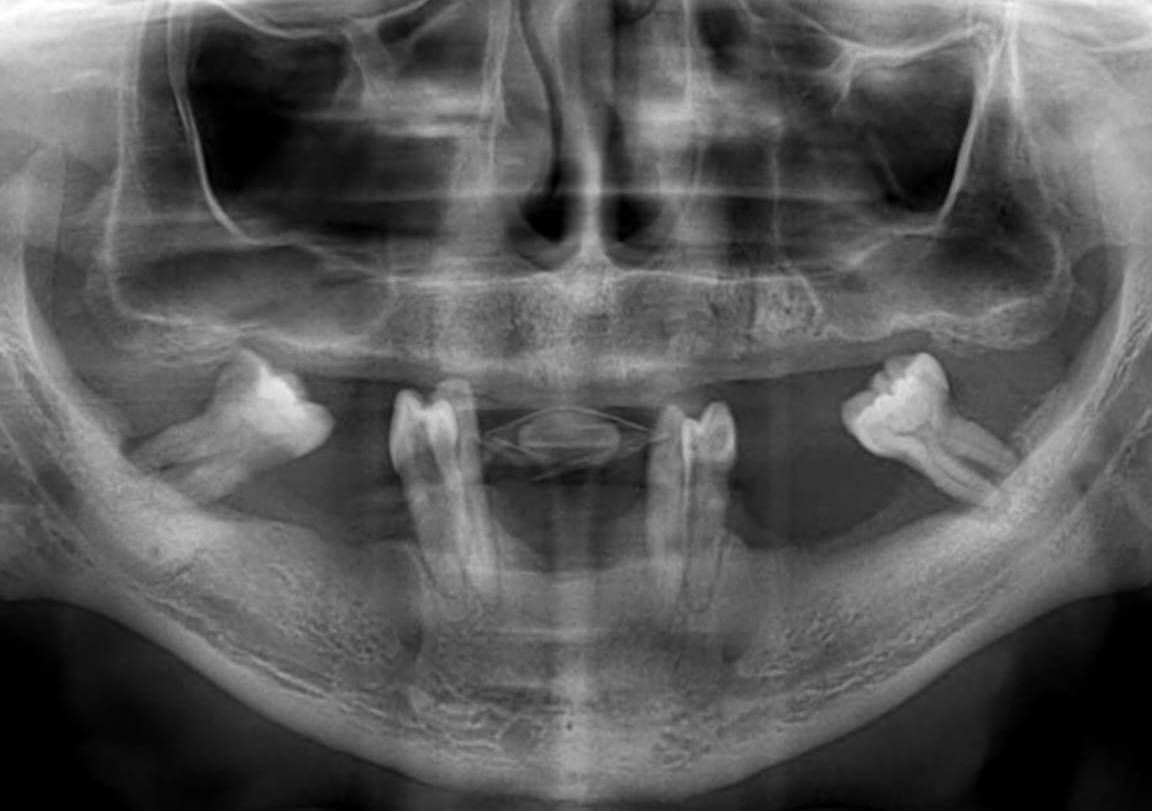

Schwerer Knochenschwund im Kiefer kann bei Patienten aus verschiedenen Gründen auftreten (Parodontalerkrankungen, Trauma, Probleme mit der Mundhygiene usw.). Bei Patienten mit fortgeschrittenem Knochenschwund ist eine herkömmliche Implantatbehandlung aufgrund unzureichenden Knochenvolumens nicht immer möglich. In solchen Fällen bieten subperiostale Implantate eine innovative und effektive Lösung.

1. Digitales Scannen und Planung

Es wird eine 3D-tomographische Aufnahme des Kieferknochens gemacht.

Anhand dieser Aufnahme wird die Knochenoberfläche millimetergenau modelliert.

Die Skelettstruktur des Subperiostaln Implantats wird individuell mit CAD/CAM-Technologie entworfen.